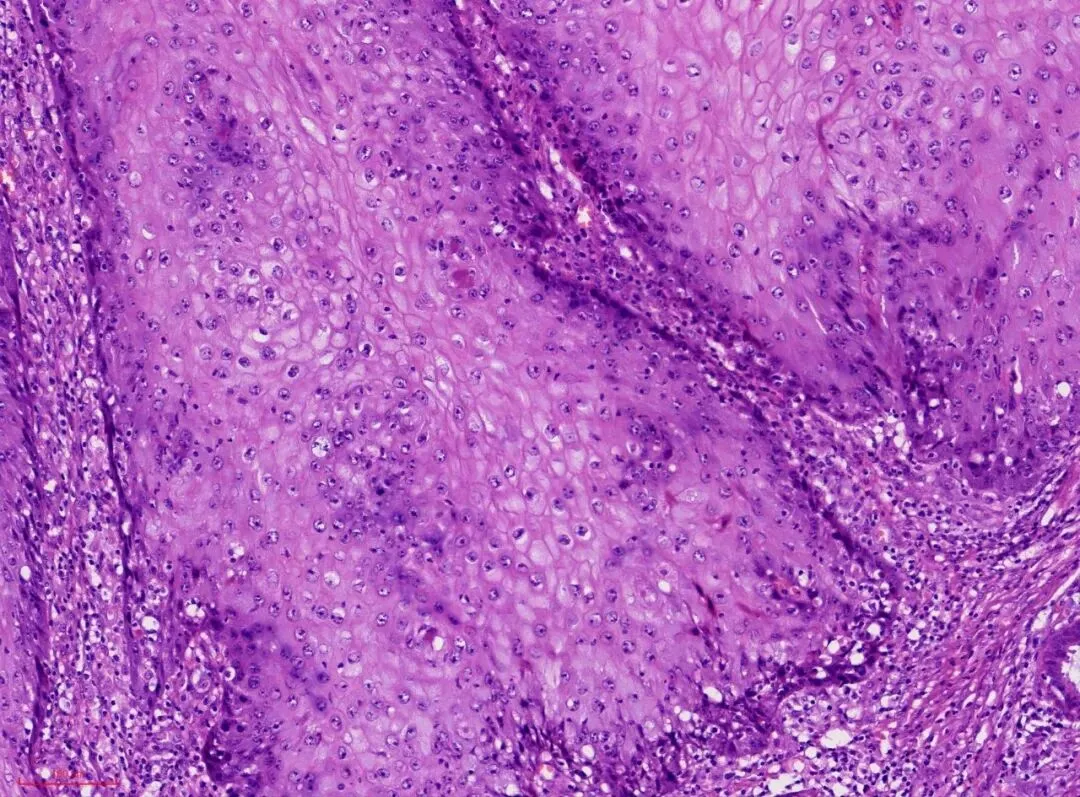

高倍镜下观察,上皮分化成熟,细胞异型性小。

2. 细胞异型性不明显